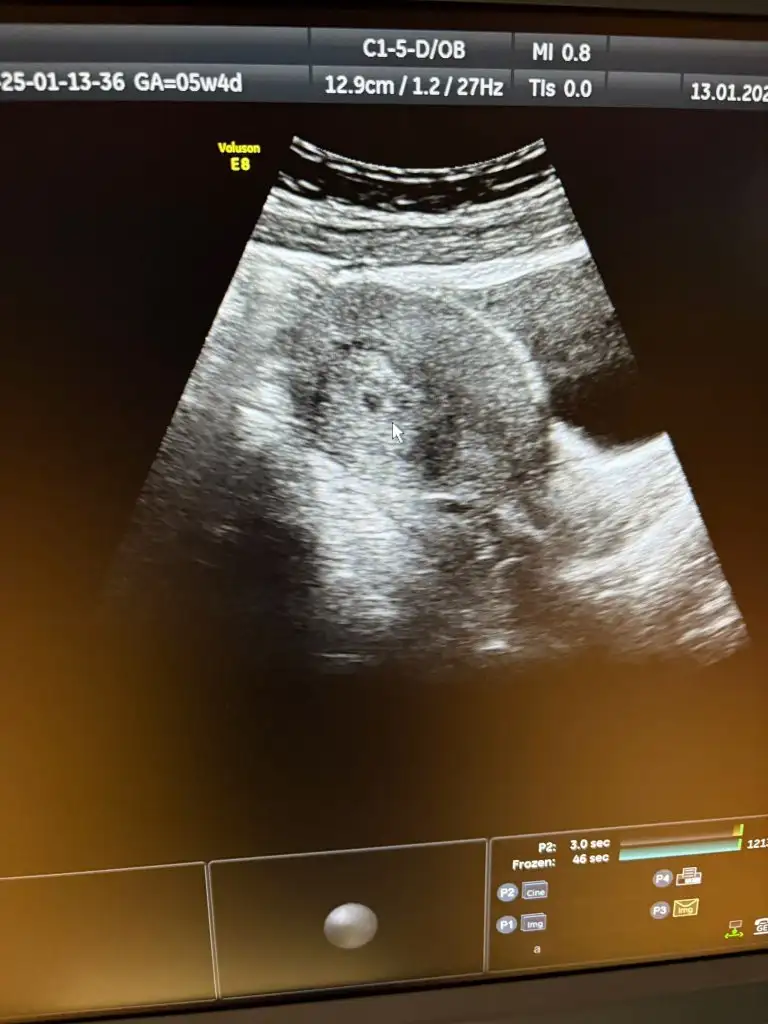

Sanırım belirli binli sayılarda belli bir sayıdan sonra %30 artış da normal diye okudum.Kızlar bugün 5+1 oldum. En son 8 ocakta beta baktırdım, 836 çıkmıştı. Cuma günü Vajinal ultrason ile kese göründü. Doktorum bugün kontrole çağırdı ve tekrar beta istedi. Karindan kesemizi gördük bugün. Haftasıyla uyumlu dedi. Ama beta hcg 9054 geldi. Normal mi bu iki kattan fazla artmış olması kötüye işaret değildir dimi ?

nolmuş birden öyle şahlanmış maşallahKızlar bugün 5+1 oldum. En son 8 ocakta beta baktırdım, 836 çıkmıştı. Cuma günü Vajinal ultrason ile kese göründü. Doktorum bugün kontrole çağırdı ve tekrar beta istedi. Karindan kesemizi gördük bugün. Haftasıyla uyumlu dedi. Ama beta hcg 9054 geldi. Normal mi bu iki kattan fazla artmış olması kötüye işaret değildir dimi ?

Hayırlı olsun canımm ben bugün 5+4 te kese gördüm ama kalp atışı için 30 ocakta gel dediKızlar herkese selam, ben de tüp bebek ile hamileyim, bu 2. Gebeliğim 8 yaşında oğlum var ama çok zaman geçti unutmuşum her şeyibugün 5+0 günümdeyim 5+4 de doktora kontrole gideceğim, sizce kalp atışı duyulur mu?